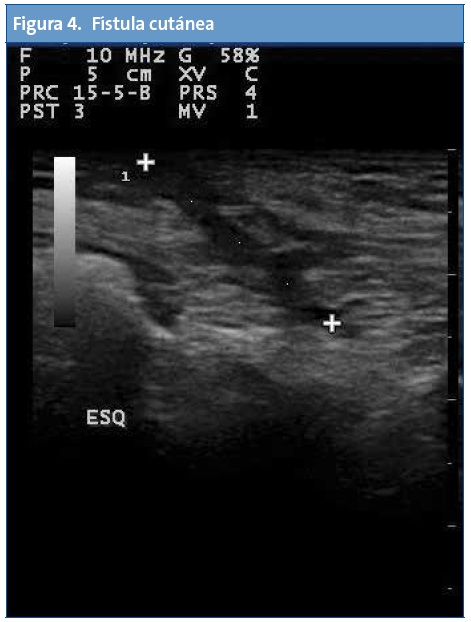

En Atención Primaria el mayor rendimiento se obtiene de la exploración abdominal seguida del estudio de la zona cervical, partes blandas, aparato genital, pulmón y aparato locomotor.